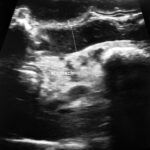

• Ultrasound. Abdominal ultrasound is a non-invasive way of estimating the size and site of the tumor. The most common place for bladder cancer in dogs is the neck of the bladder. However, variations are possible.